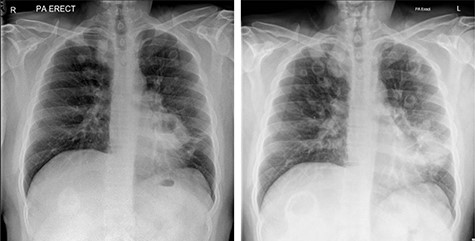

Due to persistent otalgia and two episodes of transient loss of consciousness, cross-sectional imaging by way of a CT scan was undertaken, which was unremarkable. An MR venogram however, demonstrated a right sided sigmoid sinus thrombosis, and he was commenced on treatment dose low molecular weight heparin. In conjunction with multiple specialty review and advice, an autoimmune profile was requested, which was negative, as were sputum cultures and bronchial washings for acid-fast bascilli. Due to a sustained pyrexia, multiple blood cultures as well as a trans-thoracic echocardiogram were undertaken to rule out infective endocarditis, which were again negative. Persistently raised inflammatory markers led to a CT thorax–abdomen–pelvis (TAP) request, which demonstrated multiple cavitating pulmonary nodules and widespread mediastinal nodes. Bronchoscopy and biopsy of a left upper lobe thickening merely demonstrated non-specific inflammation. With no improvement clinically, repeat MRI of the head demonstrated progression of the skull base inflammatory mass with extensive soft tissue thickening along the course of the internal carotid artery and pachymeningitis. In addition, repeat chest radiography revealed an increase in size and number of pulmonary nodules (Fig. 3).

Chest radiographs showing progression of cavitating pulmonary lesions.